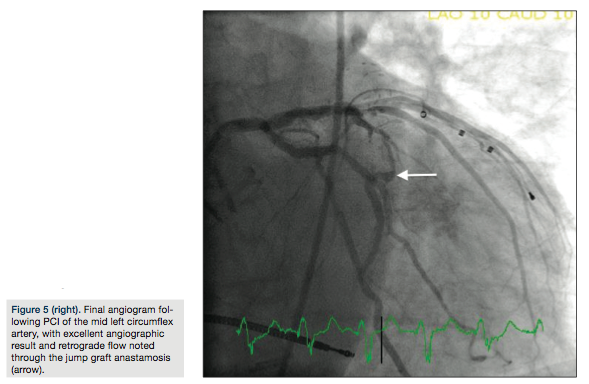

Medical) in the OM2 segment distal to the graft anastamosis (Figure 3b). A pullback FFR revealed a maximal value at 0.75 (Figure 4a) with the PressureWire wire in the OM2 segment proximal to the graft anastamosis (Figure 4b). Due to the suggestion of borderline perfusion in the distal OM2 segment despite the bypass graft, percutaneous coronary intervention (PCI) of the mid left circumflex artery was performed using a Veriflex 3.0 x 16 mm bare metal stent (Boston Scientific) with excellent angiographic result and brisk retrograde flow through the bypass graft (Figure 5).